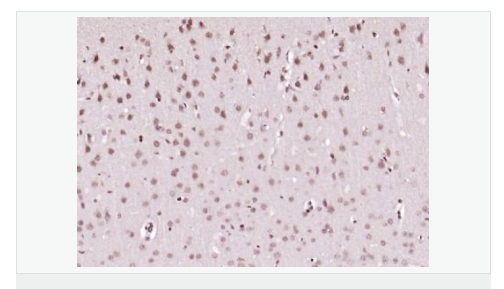

| 產品應用 | ELISA=1:5000-10000 IHC-P=1:100-500 IHC-F=1:100-500 IF=1:100-500 (石蠟切片需做抗原修復) not yet tested in other applications. optimal dilutions/concentrations should be determined by the end user. |